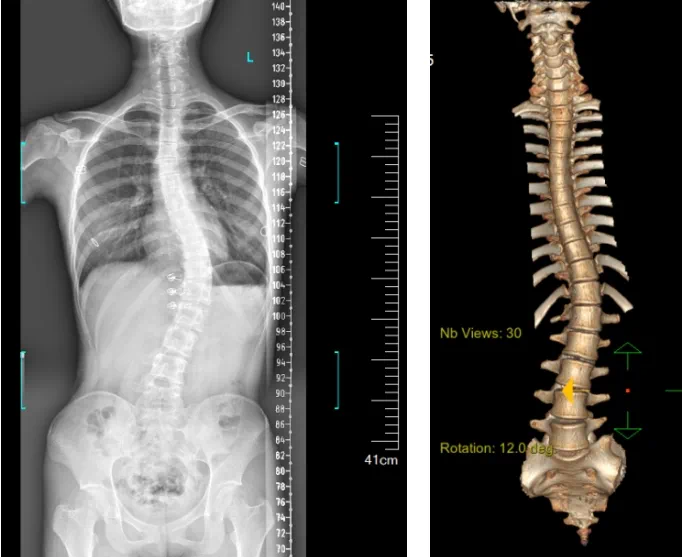

»¼ÕßΪһÃû16ËêÅ®º¢£¬·¢Ã÷¼¹Öù²àÍä1Ä꣬µ½ÄÏ·½Ò½Ôº¸ÓÖÝÒ½Ôº¼¹ÖùÍâ¿ÆÇóÕï¡£¾²éÌ壬»¼Õß×óÓÒÐØÀª²î³Ø³Æ£¬Ë«¼çµÈ¸ß£¬×ó¼çëιÇ¡Æð£¬±³²à³Ê¡°Ìêµ¶±³¡±»ûÐΣ¬ÐØÑü¶Î¼¬Í»Æ«ÀëÕýÖÐÏߣ¬ÐØÑü¶Î¼¹Öù×ó²à͹»ûÐΣ»¸÷¼¬Í»ÎÞѹʹ¼°ßµ»÷Í´£¬ÓÒ²àÑü²¿°¼ÏÝ£¬Ðظ¹¼°Ñü±³²¿¸ÐÊÜÕý³£¡£¼ì²é·¢Ã÷»¼ÕßÌØ·¢ÐÔ¼¹Öù²àÍ䣬Lenke5CÐÍ£¬Ö÷ÐØÍä51¡ã¡£»¼Õß¼°¾ìÊô¶ÔÍâ¹Û²»Öª×㣬Ϊ¸ÄÉÆÍâ¹Û¼°¹¦Ð§£¬ÒªÇóÊÖÊõ½ÃÐÎÖÎÁÆ¡£

ÔÚÓ뻼Õß¼°¾ìÊô³ä·ÖÏàͬºó£¬Õë¶Ô»¼ÕߵIJ¡Ç飬¼¹ÖùÍâ¿ÆÍŶÓÔÚ¿ÆÖ÷ÈγÂÈÙ´ºµÄÖ¸µ¼Ï£¬¾ÓÉÊõǰ×ÐϸÆÀ¹À£¬Öƶ©ÁË»úеÈ˸¨Öúϼ¹Öù²àÍä½ÃÐΡ¢Ö²¹ÇÈÚºÏÄÚÀο¿ÊÖÊõµÄÖÎÁƼƻ®£¬ÓɹùÏòÑôÖ÷ÈÎҽʦÖ÷µ¶ÊµÑé¡£

¾ÝϤ¼¹Öù²àÍäÊÖÊõÖÎÁƺó¿ÉÒÔ¼á³ÖÇû¸Éƽºâ£¬¸ÄÉÆÍâ¹Û²¢±ÜÃâ»ûÐνøÒ»²½Éú³¤¡£»¼ÕßµÄÉúÑÄÖÊÁ¿»ñµÃÌá¸ß£¬½ø¶øïÔ̼¹ÖùÌ«¹ý»ûÐοÉÄÜ´øÀ´µÄ¼²²¡µÄ±¬·¢ÂÊ£¬Íâ¹ÛÉÏµÄÆð¾¢×ª±äÍùÍùÒ²ÄÜ´øÀ´»¼ÕßÐÄÀíÓ뾫ÉñµÄÆð¾¢×ª±ä¡£ÁÙ´²ÉÏ»á×ÛºÏ˼Á¿»¼ÕßµÄÄêËê¡¢²àÍäˮƽ¡¢Ï£ÍûÇ÷ÊÆ¡¢¹ÇÖÊÌõ¼þ¡¢Ïà½ü½Ú¶ÎÇéÐΡ¢ÊÖÊõ½Ú¶ÎµÈÒòËØ£¬ºÏÀí½ÓÄɸöÐÔ»¯µÄÊÖÊõ·½·¨¾ÙÐÐÖÎÁÆ¡£È»¶ø£¬ÓÉÓÚ¼¹ÖùÉñ¾Ñª¹ÜÃܲ¼£¬ÊÖÊõ²Ù×÷Ïà¶ÔÖØ´ó£¬ÊÖÊõÄѶȸߡ¢Î£º¦´ó£¬¹Å°å¼¹Öù²àÍäµÄÊÖÊõ·½·¨ÍùÍùÓнϸߵÄÉñ¾»ò¼¹ËèËðÉËΣº¦¡£¹Ê´Ë´Î¿ÆÊÒ¾öÒ鿪չ»úеÈ˸¨Öúµ¼º½Ï¼¹Öù²àÍä½ÃÐΡ¢Ö²¹ÇÈÚºÏÄÚÀο¿ÊÖÊõ¡£Êõǰ£¬Ò½ÉúÍŶÓÔÚ»úеÈ˶àά¶ÈͼÏñÈÚºÏÖÇÄÜÊÖÊõÍýÏ빦ЧµÄ¸¨ÖúÏ£¬Ô¤ÏÈÍýÏëÁËÀíÏëµÄÖö¤Â·¾¶¡£ÊõÖУ¬Ììçá¹Ç¿ÆÊÖÊõ»úеÈË׼ȷ×ñÕÕÊõǰÍýÏ룬ƾ֤Åä׼Ч¹û£¬ÊµÊ±¶¨Î»²¢×¼È·Ö´ÐÐÖö¤²Ù×÷£¬ËùÓе¼Õë¾ùÓõç×êÖÃÈ룬һ´ÎÐÔÀֳɣ¬ÐÖúÒ½Éú˳ËìÍê³ÉÊÖÊõ¡£×îÖÕ£¬ÔÚÂé×í¿Æ¡¢ÊÖÊõÊÒÇ×½üÅäºÏÏ£¬Àúʱ3СʱÀÖ³ÉÍê³É²àÍä½ÃÐÎÊõ£¬³öѪÁ¿½ö500ml¡£Êõºó£¬»¼Õ߻ָ´ÓÅÒ죬¾Þϸ±ã¼°ÏÂÖ«Éñ¾Ô˶¯¸ÐÊÜÕý³£¡£